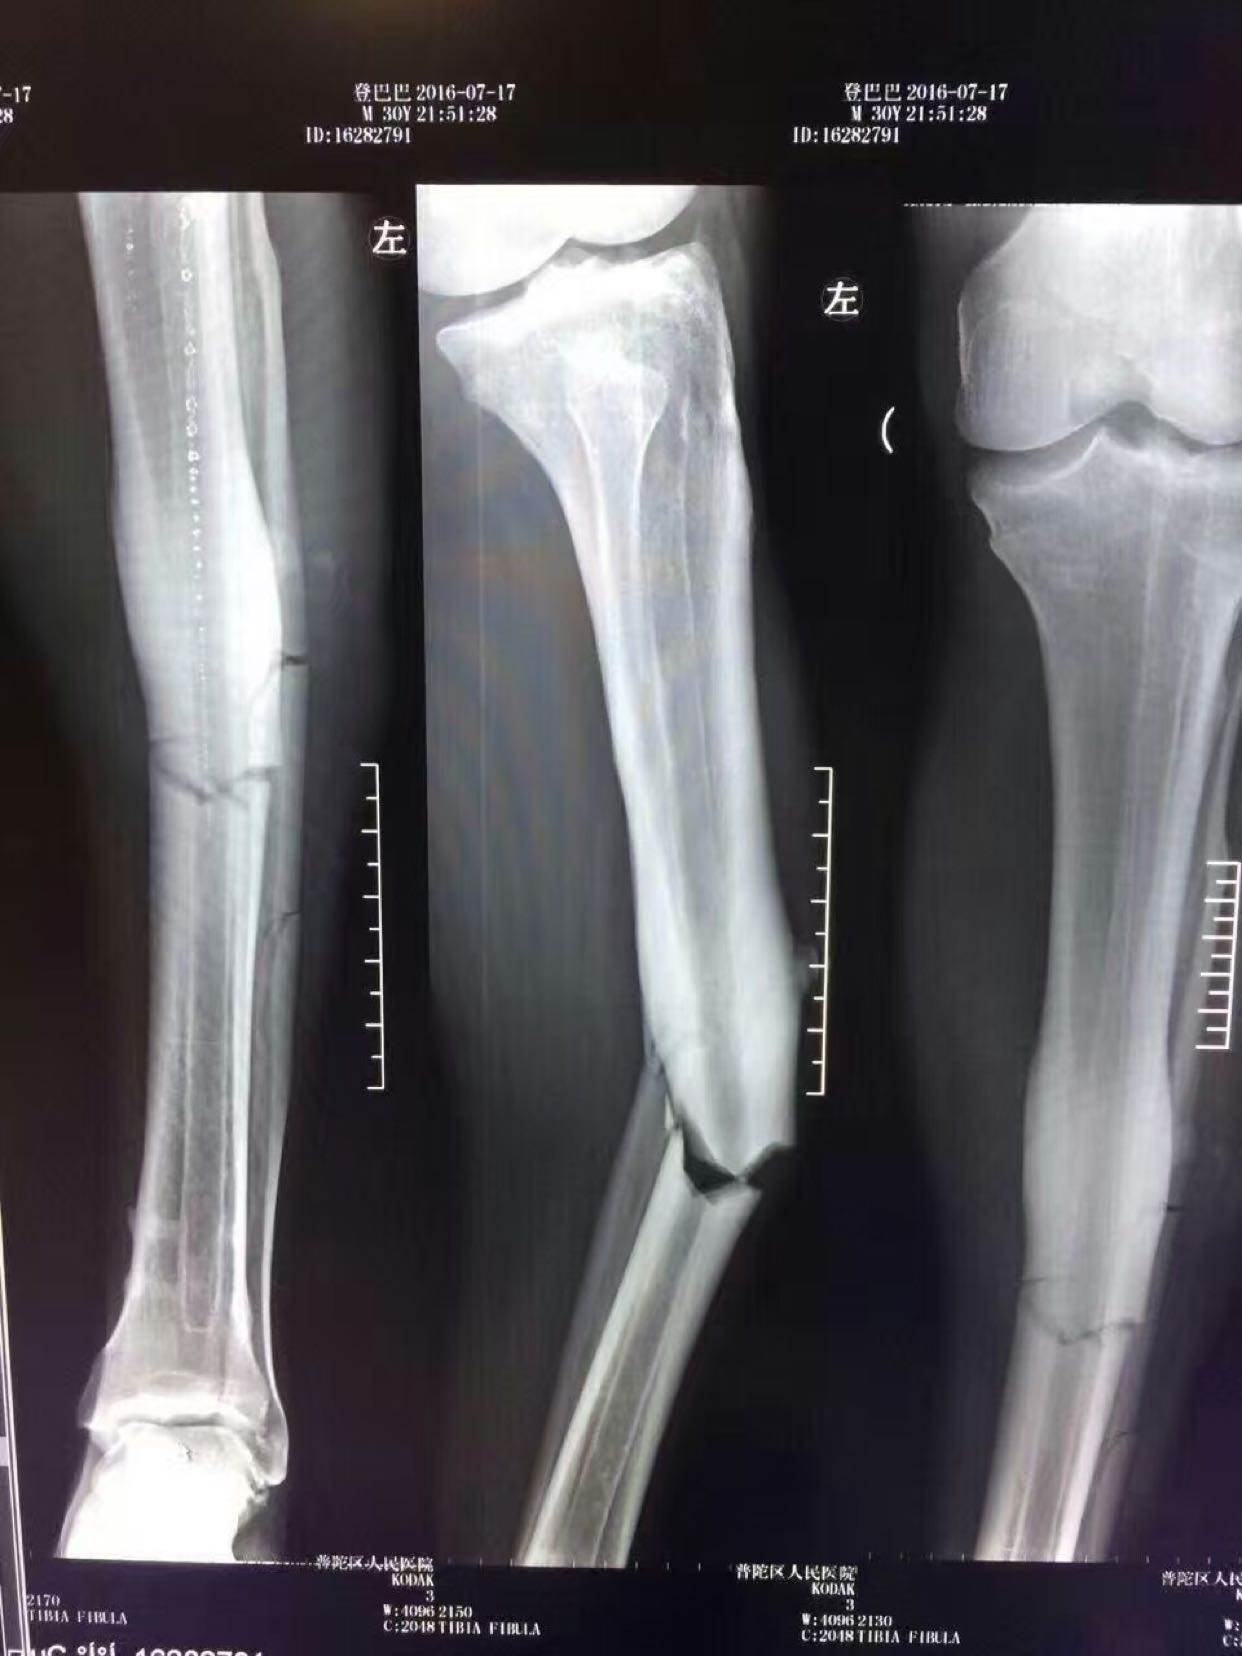

登巴巴断腿登巴巴断腿手术照片

登巴巴断腿骨折 左小腿严重变形

申花当家射手登巴巴在一次冲撞中不幸断腿,胫骨腓骨全部骨折